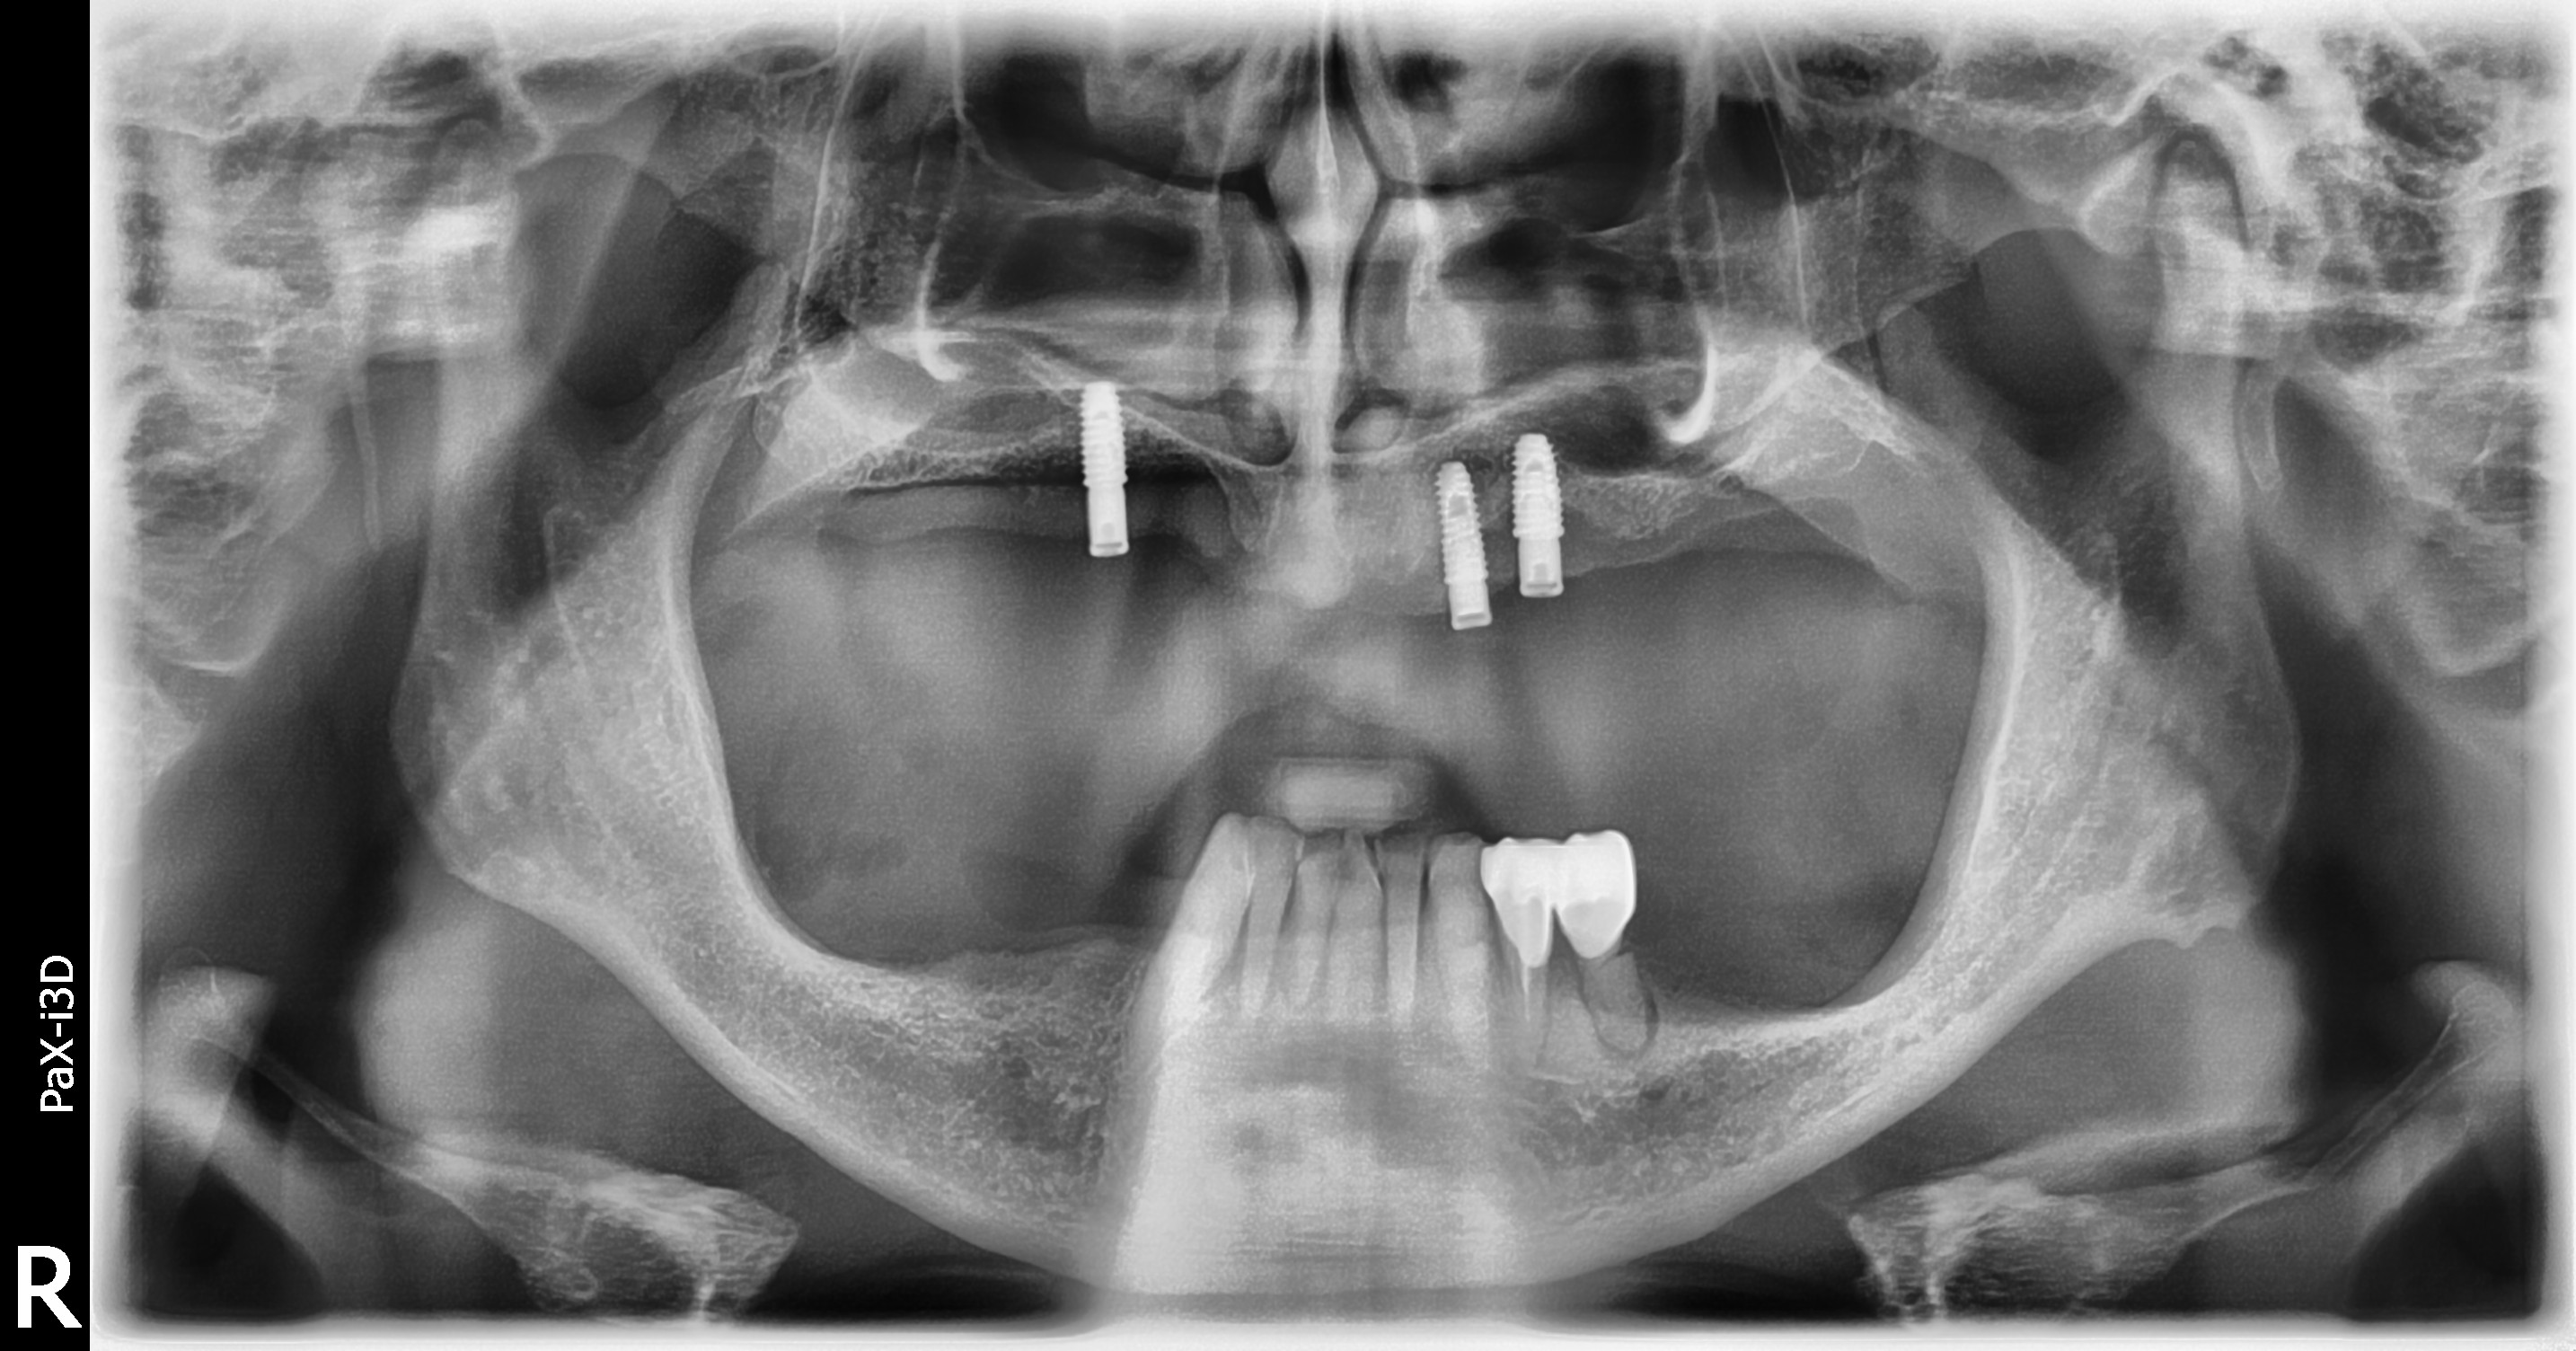

BEFOREAFTERBEFOREAFTER(식립)AFTER(착용)

임플란트 틀니

전체틀니